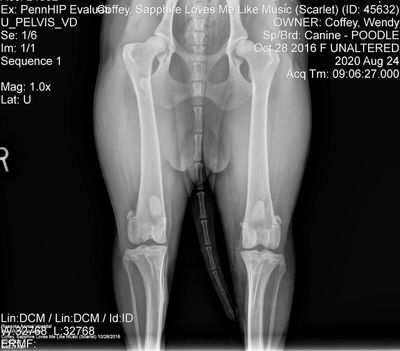

* CHIC Eligible - She has more than the required testing. She has had penn hip

testing twice, but I didn't send in to OFA. Most recent results are

in images below.

DNA tested through Optimal Selection for 150+ diseases including NEWS, vWD and DM. - All Clear. Click here to view PRA-RCD4 and Day Blindness clear. Eyes and Heart clear and listed on OFA site. Hips xrayed at 2, and again at 3 years 10 months. Most recent xray at left. No radiographic evidence of HD, average distraction index (.48-.50). Results below in image gallery.